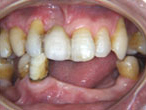

初診時

上下顎に数本の歯が残っていますが咬合支持がほとんどないために満足に食事もできない状態でした。また、下顎前歯部から臼歯部にかけて骨吸収が進行しており、上顎臼歯部にインプラント治療を行うためには骨造成が必要な状態です。

正面